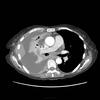

huge effusion CT

Date: 09/24/2006

Views: 5364